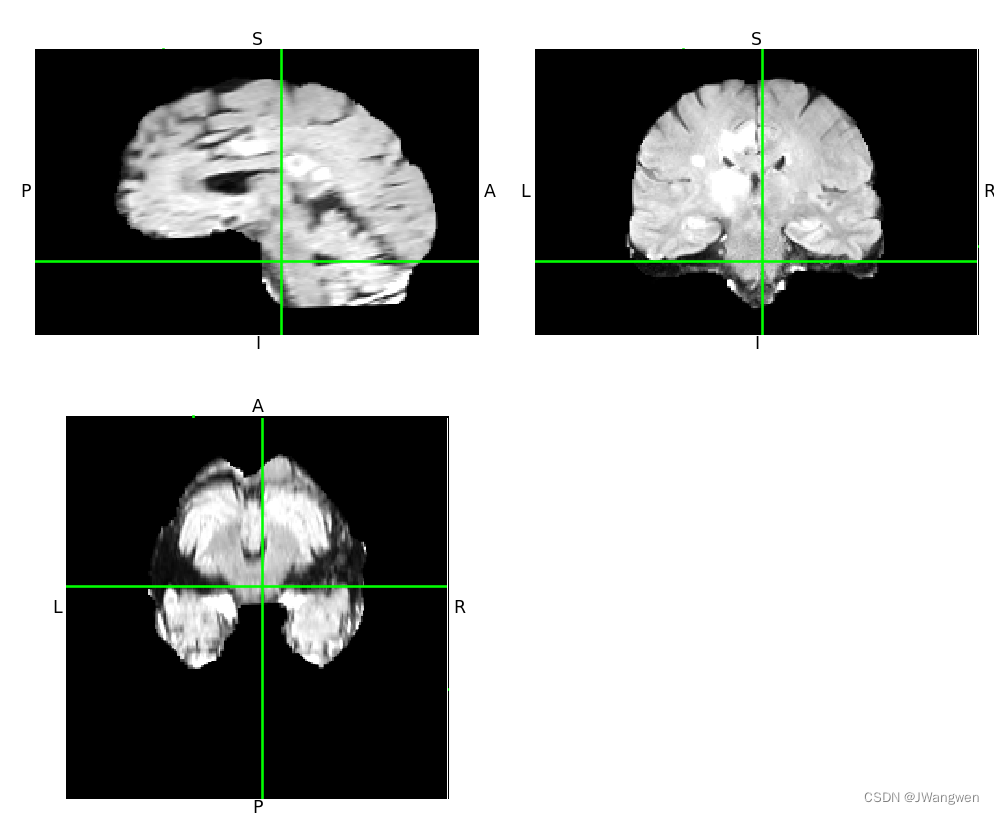

nib.viewers.OrthoSlicer3D(img.dataobj).show()

显示图片如下:(如果是黑色,鼠标拖动一下图片或者动一下滚轮,可能是坐标在原点)

两种方式好像第二种会显示的的是3D的,更多态化一点,光是看一下数据长什么样子的话,两种方式都能用